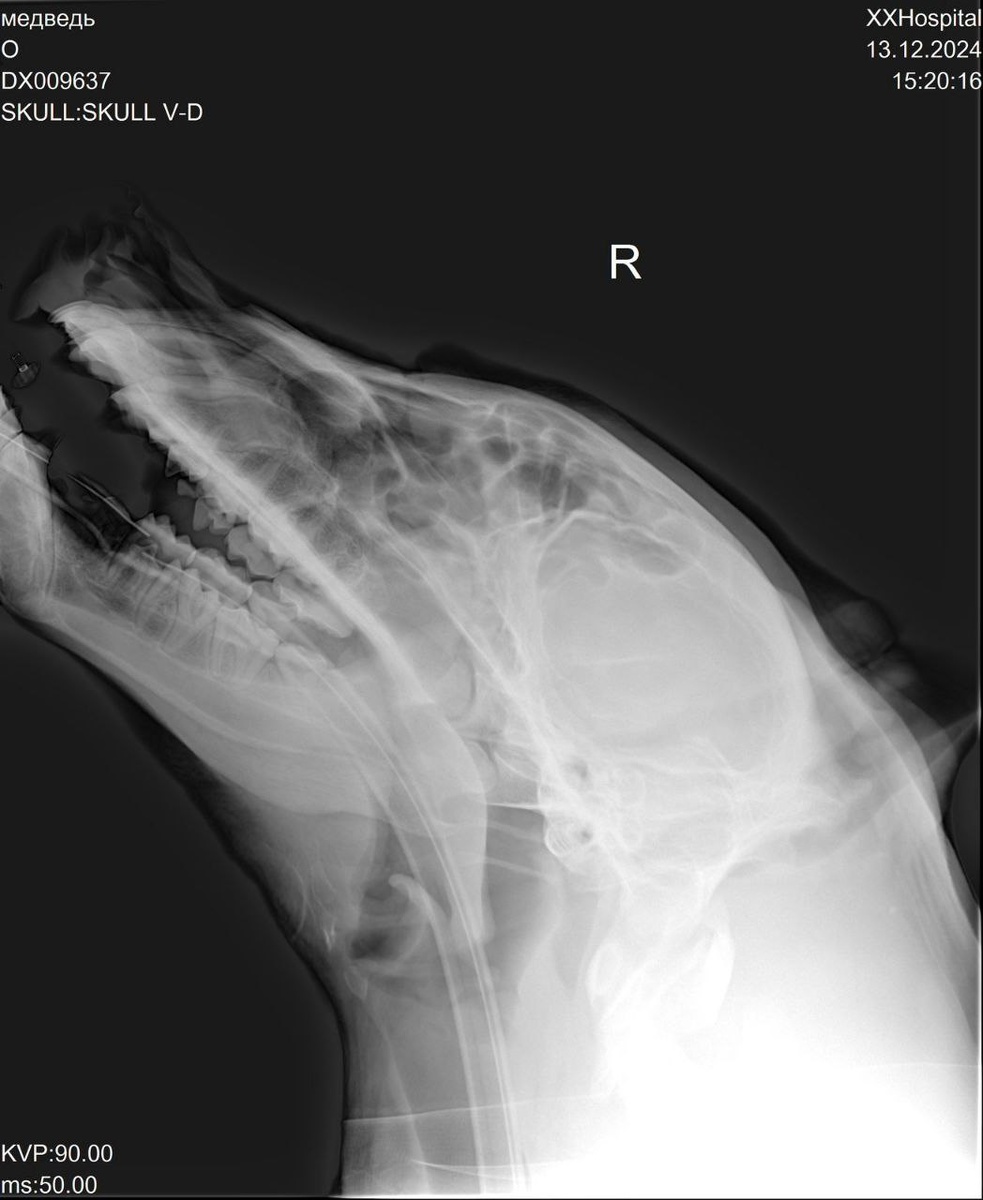

По поводу лечения тут говорят, что пока еще все находится в процессе. Последние анализы крови Мишки ничего критичного не показали, а благодаря рентгену удалось исключить возможное нахождение инородного тела. Сейчас на руках у приюта есть результаты эндоскопического исследования пазух носа, оно показало затемнение. Вероятно — воспаление. Волонтеры ожидают еще и результатов гистологии.

Фото: «Дино», мишке сделали наркоз и везут в клинику